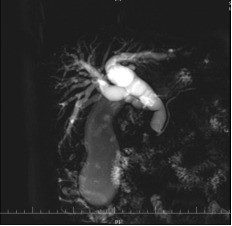

患者金大爷,因梗阻性黄疸到我院就诊收住消化内科,完善相关检查后发现胆管占位性病变 ,胆总管下段壁稍增厚,低位胆道梗阻待鉴别;腹腔内及腹膜后淋巴结增多部分稍增大;肝脏多发囊性病变待排;胆囊稍肿大并胆汁浓缩。经院内会诊后,患者转入普外二科继续下一步治疗。我院普外二科主任李国松向患者及家属详细讲解病情的复杂性和手术的必要性,在排外手术禁忌后,拟定了高难度的手术方案——腹腔镜下胰十二指肠切除术+肝病损切除术+胆囊切除术。 在做好充分术前准备的基础上,普外二科手术团队披上“绿战袍”,向腹部手术的“珠穆朗玛峰”发起挑战。

在手术室麻醉团队和护理团队的配合下,历时8小时41分钟,手术取得成功。医护团队默契配合、精准操作,术中出血量仅为200ml,术后患者麻醉苏醒后安返病房。在全体医护人员的精心治疗和护理下患者恢复良好顺利出院。